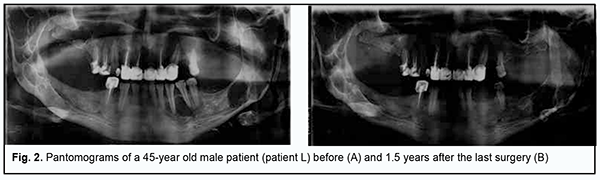

Facial skin was clear and of a normal color. Submandibular, submaxillary, submental and neck lymph nodes were not enlarged. Mandibular motility was within normal limits. The mucosa of the oral vestibule and oral cavity was moderately moist and pale pink. In the adult patients, there was anodontia of the mandible and maxilla. Prostheses were used to restore the integrity of dentitions and normal occlusion. The children had late mixed occlusion. In the adult patients, no malformation was found on palpation of the alveolar processes of the jaws at both sides. In both children, dome-shaped malformations of the vestibular lamina of the maxilla at the areas of lesions were found on palpation. In addition, in one the boys, malformation in the post-operative site on the mandible was found on palpation. Both adults underwent their last surgery 5 to 7 years before, with their pantomograms showing anodontia of the lateral mandible and maxilla. Heterogeneous bone density with poorly delineated post-operative areas of restored bone tissue prevailed. In the man, the X-ray at 1.5 years after surgery showed a well-defined cyst-like mass in the right mandibular ramus, close to the condylar neck, with the mass showing no progression compared to previous X-rays (Figure 2).